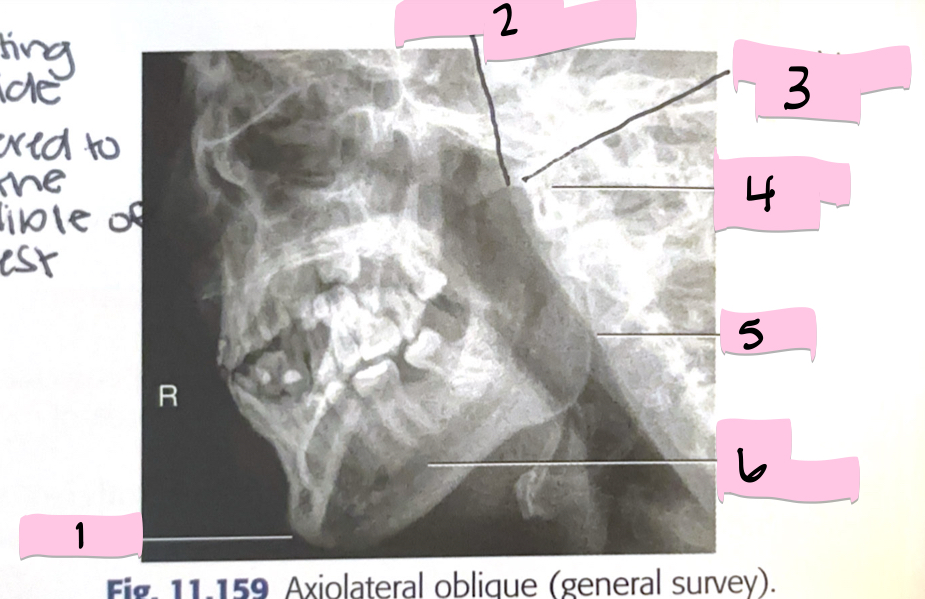

What is 1 pointing to?

Frontal sinus

What is 2 pointing to?

Superior orbital fissure

What is 3 pointing to?

Bony nasal septum

What is 4 pointing to?

Anterior nasal spine

What is 5 pointing to?

Crista galli

What is 6 pointing to?

Petrous ridge

What is 7 pointing to?

Floor of orbit

What is 8 pointing to?

Maxillary sinus